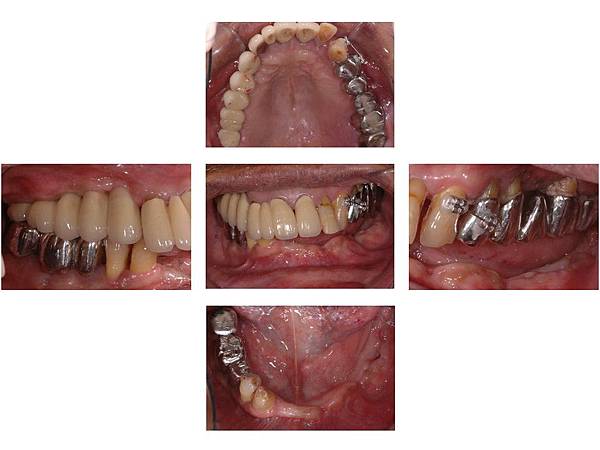

牙周病全口重建病例3

牙周病全口重建病例2

牙周病全口重建病例1